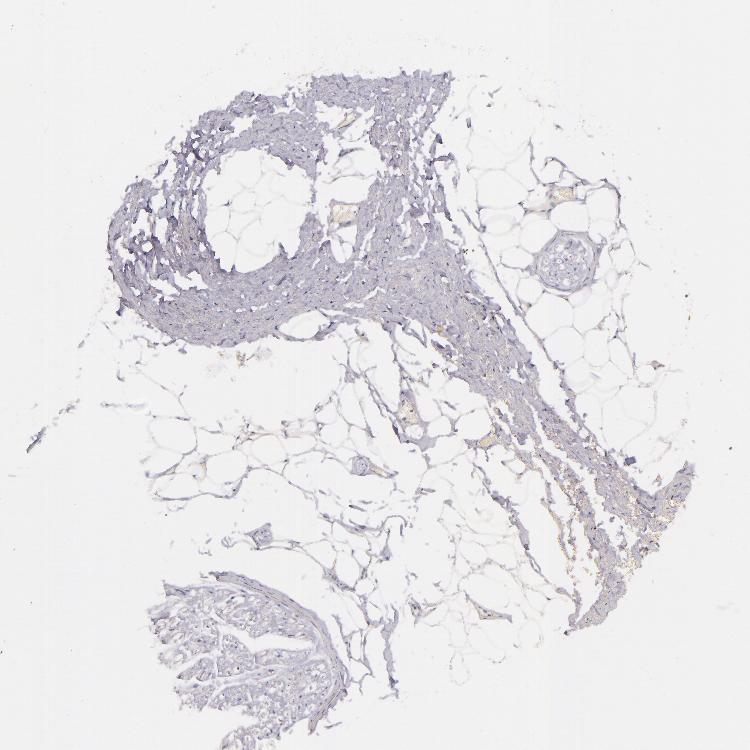

TISSUE PRIMARY DATA SOFT TISSUE Show tissue menu

SOFT TISSUE - Expression summary

SOFT TISSUE 1 - Antibody stainingi

Antibody staining in the annotated cell types in the current human tissue is reported as not detected, low, medium, or high, based on conventional immunohistochemistry profiling in selected tissues. This score is based on the combination of the staining intensity and fraction of stained cells.

Each image is clickable and will lead to virtual microscopy that enables deeper exploration of all samples and also displays staining intensity scores, fraction scores and subcellular localization as well as patient and tissue information for each sample.

Antibody HPA000425Antibody HPA002017

Fibroblasts Not detected-

Peripheral nerve Not detectedNot detected